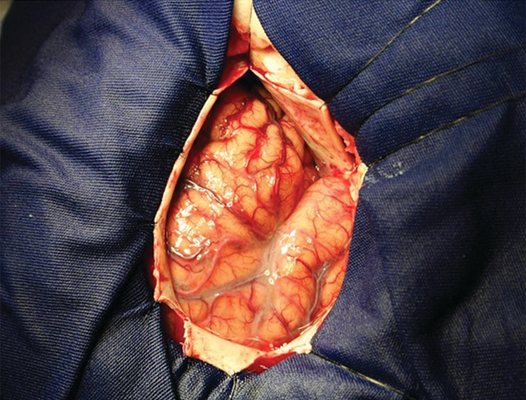

顱內血腫圖片

硬膜下血腫 (7)

硬膜下血腫 (8)

硬膜下血腫 (9)